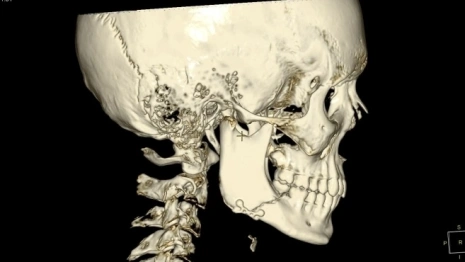

Подростку потребовалась операция. Челюстно-лицевой хирург исправил ему перелом нижней челюсти. А ЛОРы устранили перелом носа.